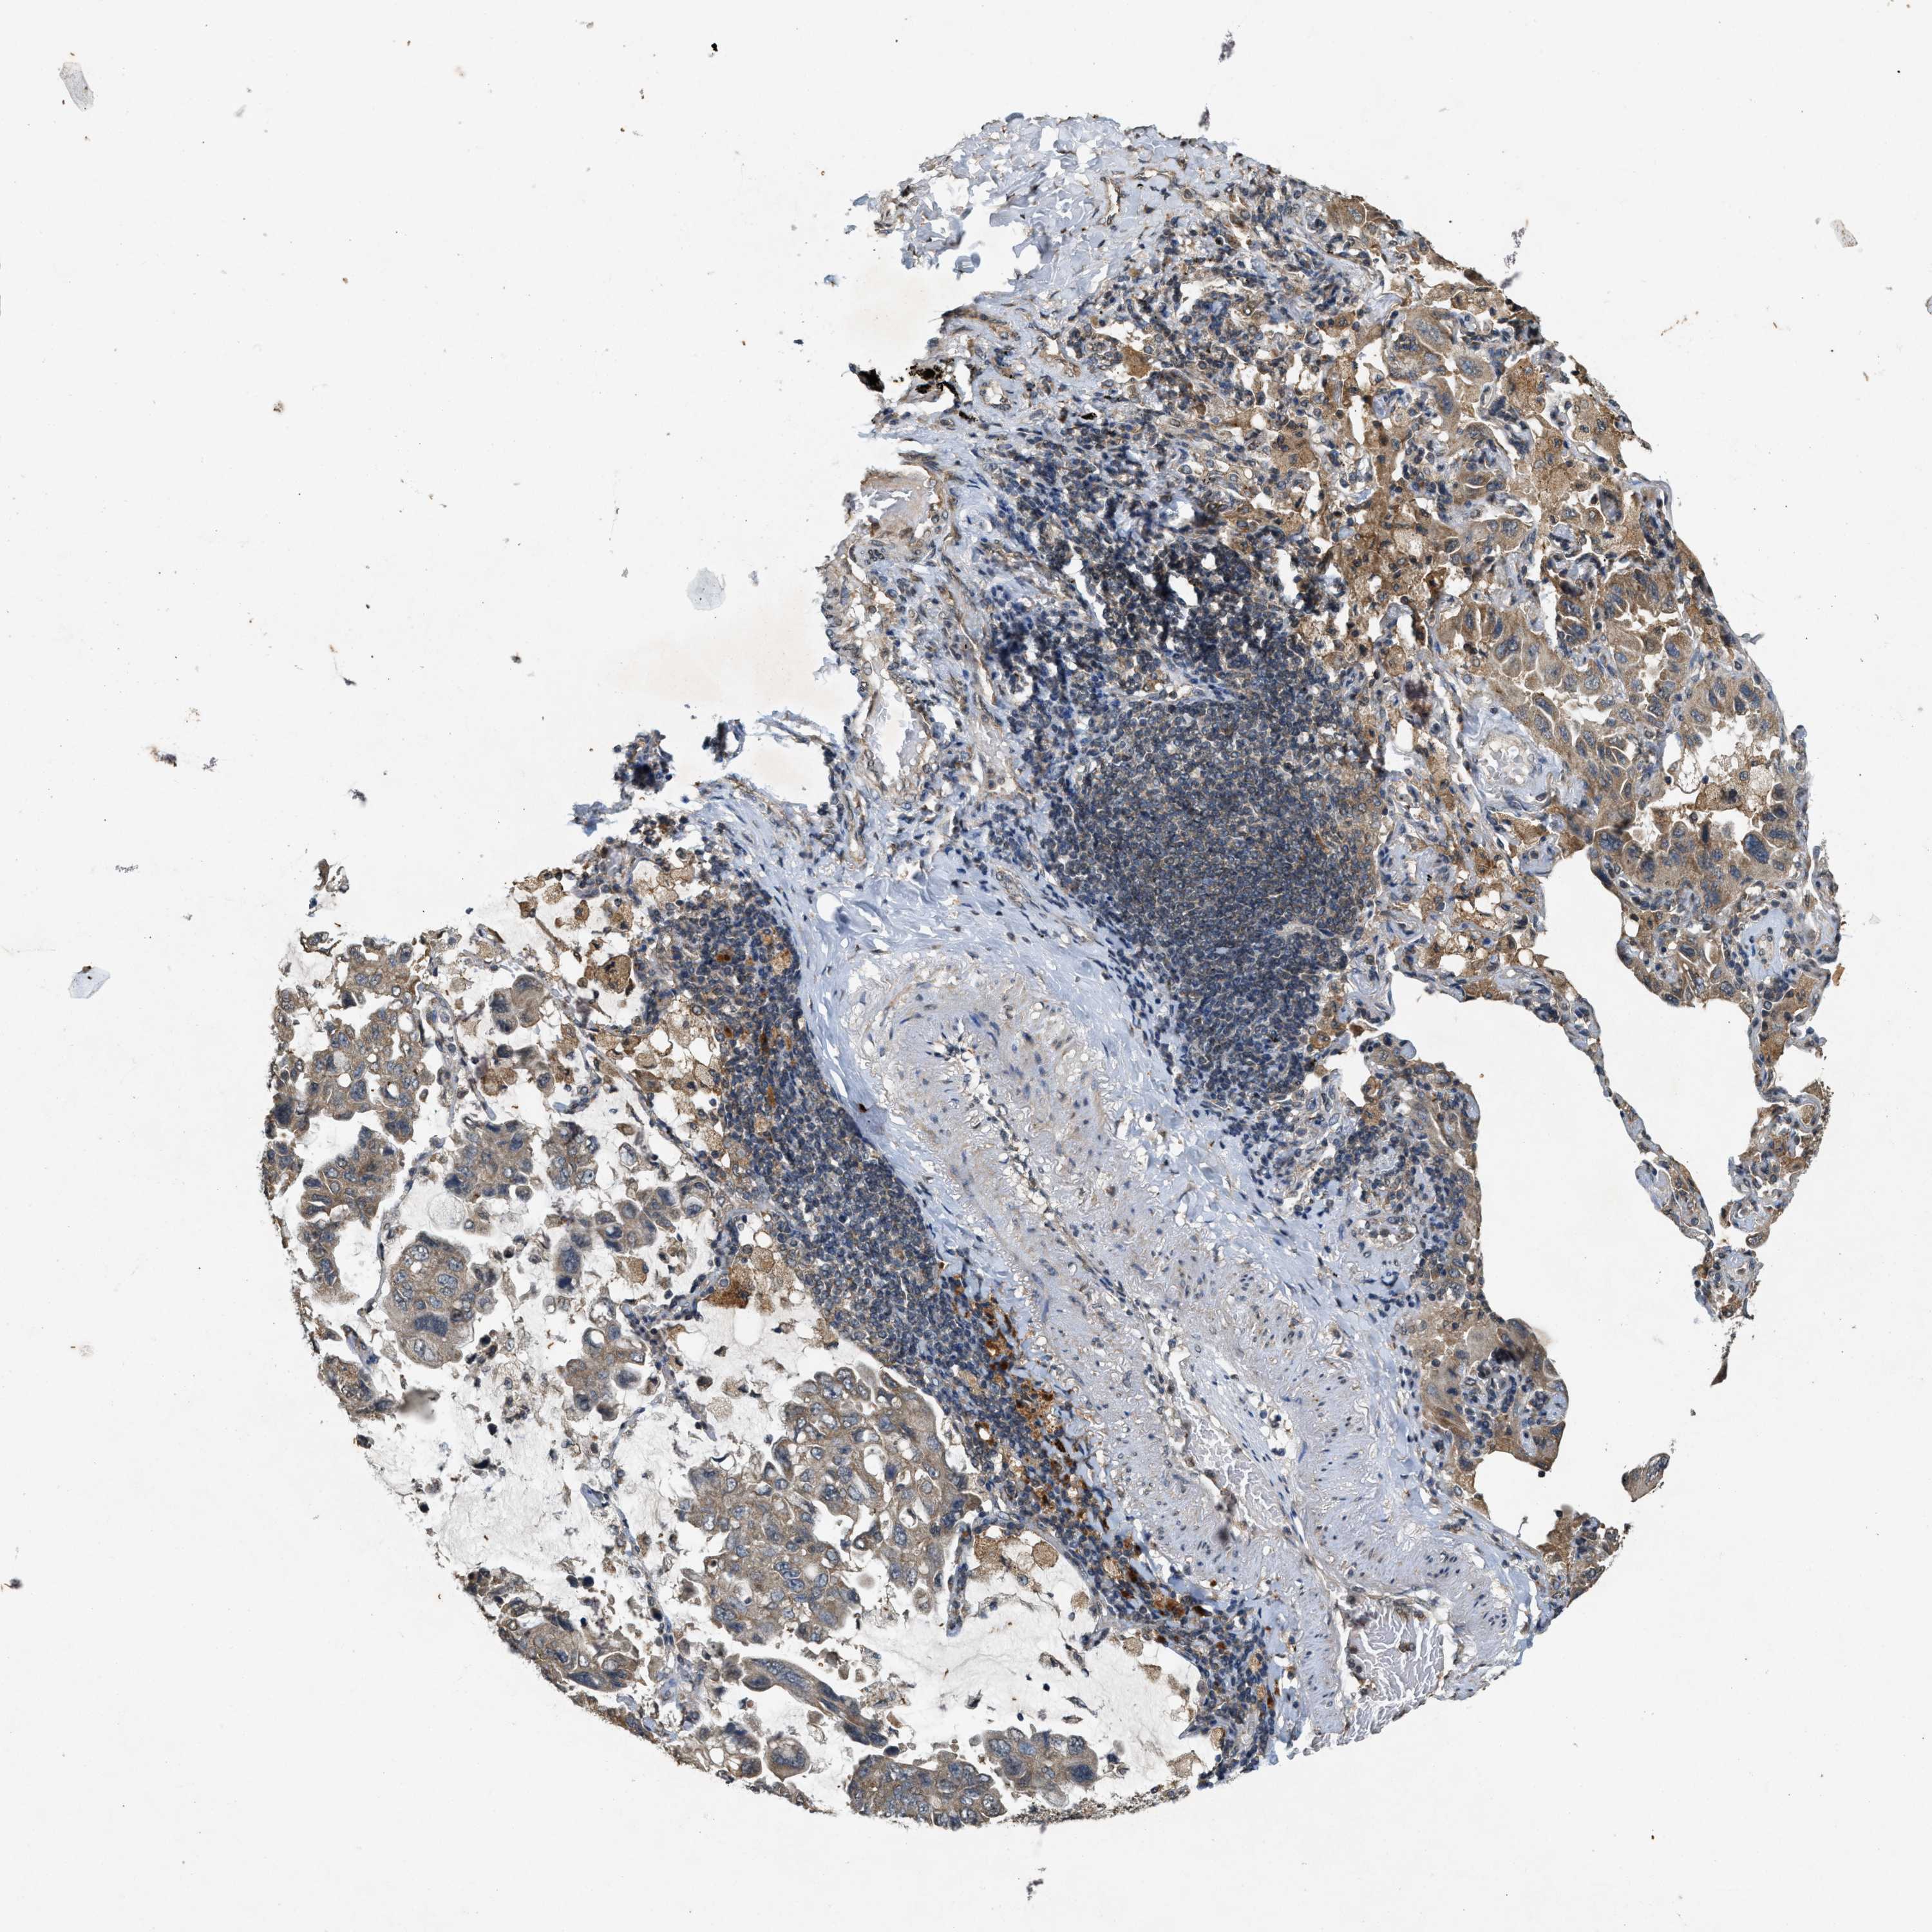

LUNG ADENOCARCINOMA (VALIDATION) - Interactive survival scatter ploti

The Survival Scatter plot shows the clinical status (i.e. dead or alive) for all individuals in the patient cohort, based on the same data that underlies the corresponding Kaplan-Meier plots. Patients that are alive at last time for follow-up are shown in blue and patients who have died during the study are shown in red.

The x-axis shows the expression levels (FPKM) of the investigated gene in the tumor tissue at the time of diagnosis. The y-axis shows the follow-up time after diagnosis (years). Both axes are complimented with kernel density curves demonstrating the data density over the axes. The top density plot shows the expression levels (FPKM) distribution among dead (red) and alive patients (blue). The right density plot shows the data density of the survived years of dead patients with high and low expression levels respectively, stratified using the cutoff indicated by the vertical dashed line through the Survival Scatter plot. This cutoff is automatically defined based on the FPKM cutoff that minimizes the p-score. The cutoff can be changed by dragging the vertical line or by entering a cutoff value in the square labeled "Current cut-off".

Under the Survival Scatter plot the p-score landscape (black curve; left axis) is shown together with dead median separation (red curve; right axis). Dead median separation is the difference in median mRNA expression between patients who have died with high and low expression, respectively. It is calculated as follows: median FPKM expression of dead patients with high expression - median FPKM expression of dead patients with low expression. This is intended to aid the user in visually exploring custom cutoffs and the associated p-scores and dead median separation.

Individual patient data is displayed and can be filtered by clicking on one or more of the category buttons on the top of the page. Categories describing expression level and patient information include: high, low, alive, dead, female, male and tumor stages. The scale of the x-axis can be toggled between linear and log-scale by clicking on the "x log" button. Mouse-over function shows TCGA ID, patient information and mRNA expression (FPKM) for each patient.

& Survival analysisi

Kaplan-Meier plots summarize results from analysis of correlation between mRNA expression level and patient survival. Patients were divided based on level of expression into one of the two groups "low" (under cut off) or "high" (over cut off). X-axis shows time for survival (years) and y-axis shows the probability of survival, where 1.0 corresponds to 100 percent.

KIF21A is not prognostic in Lung Adenocarcinoma (validation)

Best expression cut offi

Based on the FPKM value of each gene, patients were classified into two groups and association between prognosis (survival) and gene expression (FPKM) was examined. The best expression cut-off refers the FPKM value that yields maximal difference with regard to survival between the two groups at the lowest log-rank P-value. Best expression cut-off was selected based on survival analysis .

When clicking on this number, the vertical dashed line indicating cut-off, the interactive survival plot, and the Kaplan-Meier curve will be adjusted to show results based on the best expression cut-off.

: 15.09

P scorei

Log-rank P value for Kaplan-Meier plot showing results from analysis of correlation between mRNA expression level and patient survival.

N/A

TCGA RNA samplesi

RNA-seq data is reported as average FPKM (number Fragments Per Kilobase of exon per Million reads), generated by the The Cancer Genome Atlas (TCGA) .

Normal distribution across the dataset is visualized with box plots, shown as median and 25th and 75th percentiles. Points are displayed as outliers if they are above or below 1.5 times the interquartile range. FPKM values of the individual samples are presented next to the box plot.

Average pTPM 18.1

Number of samples 105